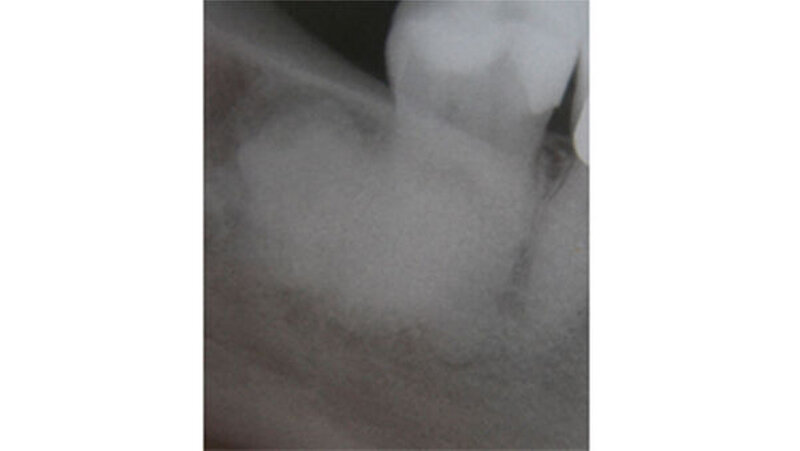

Eine 65-jährige beschwerdefreie Patientin stellte sich zur Routineuntersuchung in unserer Praxis vor. Diagnostiziert wurde eine generalisiert moderate, lokalisiert schwere chronische Parodontitis. Die im Rahmen der parodontalen Vorbehandlung durchgeführte Röntgendiagnostik zeigte eine haselnussgroße wolkige Verschattung regio 48. Anamnestisch wurde eine operative Entfernung des Weißheitszahns 48 vor ungefähr 35 Jahren angegeben.

Klinisch zeigte sich, dass die knöcherne Veränderung nicht mit Blutgefäßen durchsetzt war. Erst nach vollständiger Entfernung konnte in der Defekttiefe aus der angrenzenden lingualen Spongiosa eine Blutung provoziert werden. Histologisch wurde ein Osteom aus kompaktem, regressiv verändertem Lamellenknochen mit überwiegend leeren Osteozytenlakunen sowie sehr vereinzelt unreifes Osteoid mit aktivierter Bindegewebszone nachgewiesen.